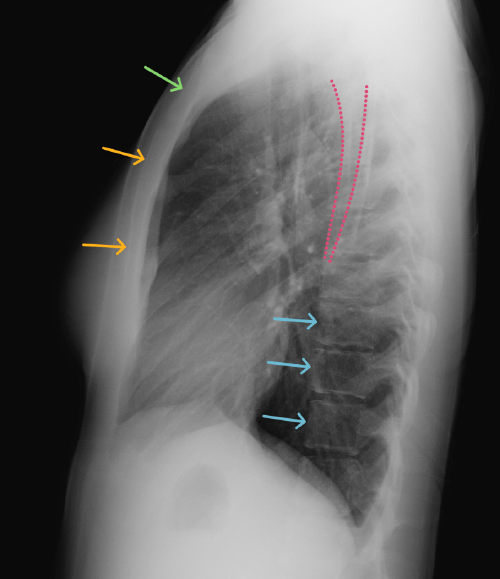

Chest

Chest

Chest radiograph & CT anatomy

Chest

Chest

Chest radiograph & CT anatomy